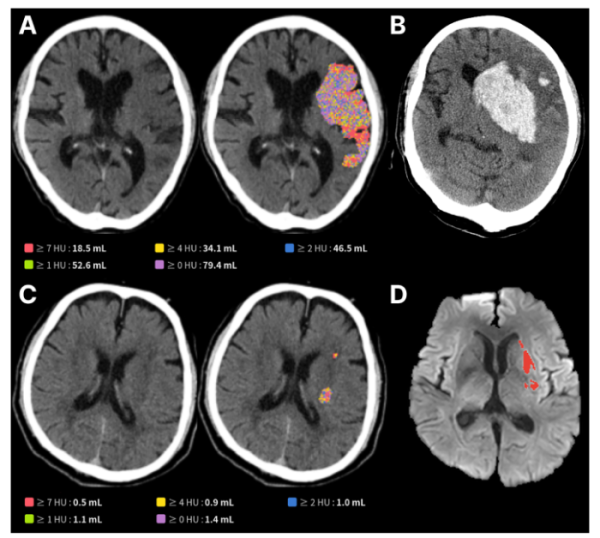

뇌졸중 환자가 응급실에 오면 가장 먼저 촬영하는 검사는 NCCT다. 접근성이 높지만 초기 병변이 미세해 육안 판독에 한계가 있고, 의료진의 경험에 따라 결과가 달라질 수 있다. 제이엘케이는 NCCT와 확산강조 영상 데이터를 학습한 AI 모델을 통해 미세한 뇌 손상 영역을 자동 검출하고, 그 범위를 정량적으로 분석할 수 있도록 했다.

이번 연구는 국내 6개 권역 뇌졸중 센터에서 혈관 재개통술을 받은 603명 환자 데이터를 기반으로 진행됐다. 분석 결과 AI가 측정한 뇌 손상 부피가 클수록 3개월 후 기능 회복 가능성은 현저히 낮았으며(50mL 초과 시 17.3% vs. 54.2%), 뇌출혈 같은 합병증 위험은 높게 나타났다(66.0% vs. 46.3%). 이는 응급실에서 흔히 사용하는 CT만으로도 환자의 장기 예후를 예측할 수 있음을 보여주는 근거다.